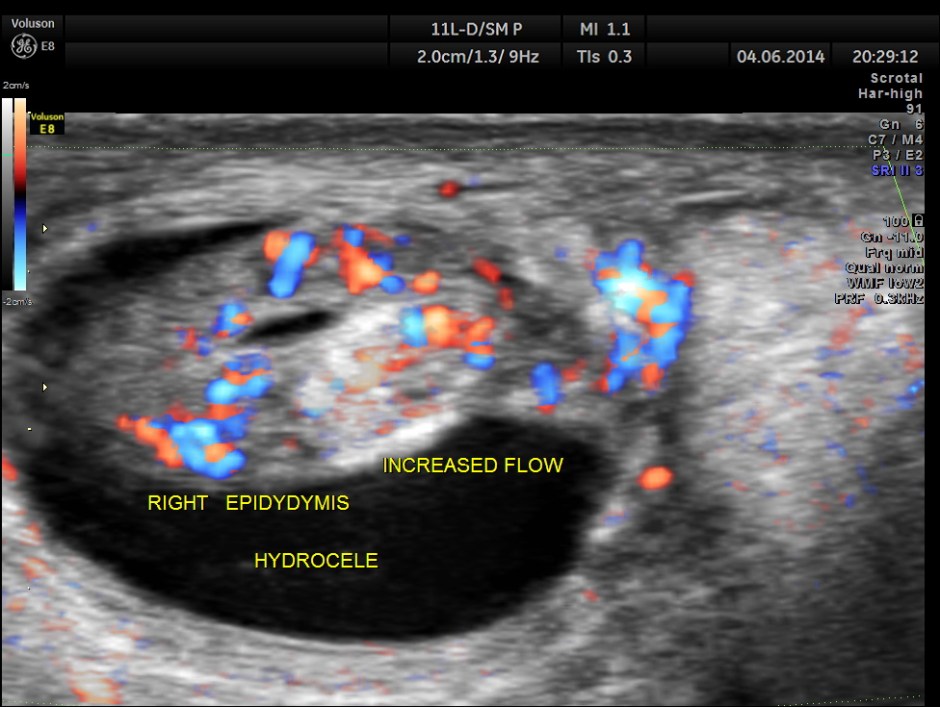

This was a 9-year-old boy , who was referred for evaluation of acute right scrotal pain of 2 days onset. He had mild right scrotal swelling and severe pain . One of the best uses of colour Doppler is for evaluation of acute scrotal pain , when the surgeon wants to rule out acute torsion . The other common condition is acute inflammation , which is medically managed. The images with colour just tell the story .

Rt Testis has normal appearance , with enlargement of the right epididymis . Colour flow imaging shows normal flow in the scrotum and increased flow in the epididymis , suggestive of acute inflammation – Acute Epididymitis.

Mild hydrocele is also seen.